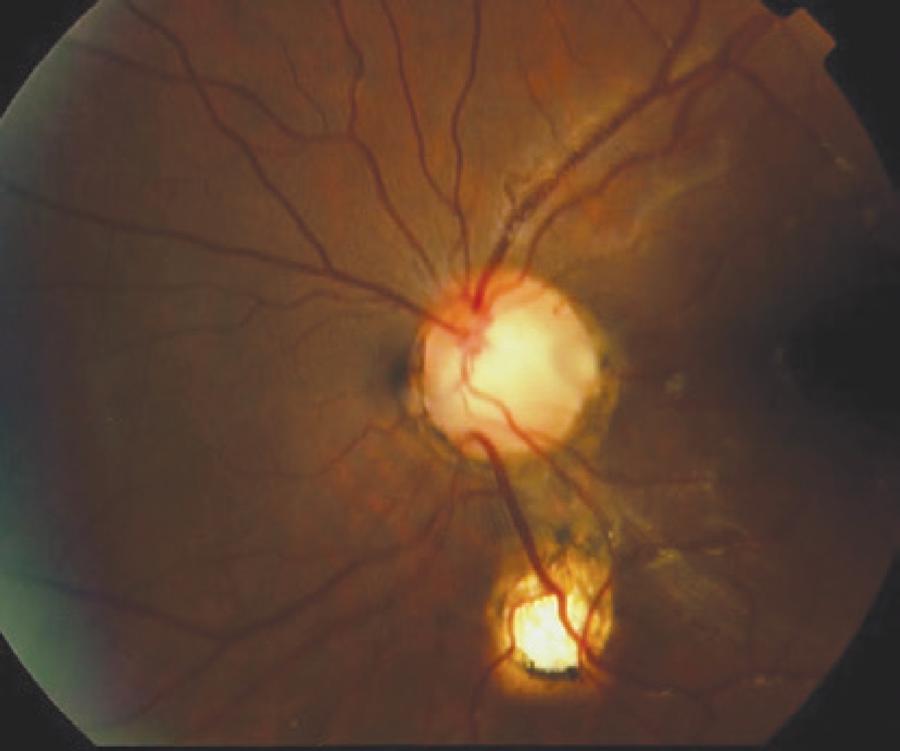

A 21-year-old man presented at our clinic for a routine bilateral ophthalmologic examination. His BCVA was 20/20 in the right eye and 20/50 in the left eye, with a refraction of -4.00. Bilateral biomicroscopic examination was normal. Intraocular pressure was 12 mmHg in the right eye and 9 mmHg in the left eye. Fundus examination of the left eye revealed an oval and gray inferotemporal optic pit and a choroid coloboma with half the size of an optic disc that was inferior to the optic nerve head. Additionally, two cilioretinal arteries were detected, one of which transited through the optic pit (Figure 4). The macula was normal, and there was no retinal detachment in the left eye. The fundus of the right eye was normal.